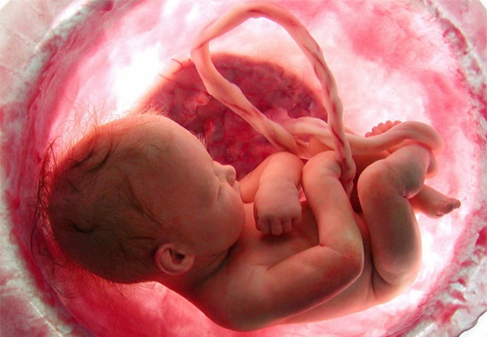

Thai giới hạn tăng trưởng trong tử cung, tình trạng mà các mẹ bầu hay gọi là thai suy dinh dưỡng, là khi cân nặng (kích thước) thai nhi nhỏ hơn mong đợi so với số tuần tuổi thai. Thai giới hạn tăng trưởng có thể xảy ra ở bất kỳ thời điểm nào trong thai kỳ. Thai nhi không phát triển tốt từ kích thước tổng thể cho đến phát triển các tế bào, mô, cơ quan. Điều này sẽ gây ra nhiều vấn đề cho em bé.

Nguyên nhân chính là do thai nhận không đủ dinh dưỡng. Để dinh dưỡng đến và được thai sử dụng để lớn lên, quá trình này trải qua nhiều công đoạn. Đầu tiên, dinh dưỡng cho thai bắt nguồn từ máu mẹ. Dinh dưỡng và oxy sau khi được hấp thu vào máu mẹ sẽ được vận chuyển đến tử cung và đổ vào các hồ máu tại bánh nhau. Sau đó là quá trình trao đổi dinh dưỡng tại bánh nhau và vận chuyển dinh dưỡng đến thai thông qua dây rốn. Các động mạch rốn mang máu nghèo oxy (từ thai) đến trao đổi chất tại các hồ máu bánh nhau (lấy chất dinh dưỡng từ máu mẹ), sau đó mang máu giàu oxy và dinh dưỡng qua tĩnh mạch rốn đến thai nhi. Cuối cùng, thai nhi sử dụng dinh dưỡng để phát triển.